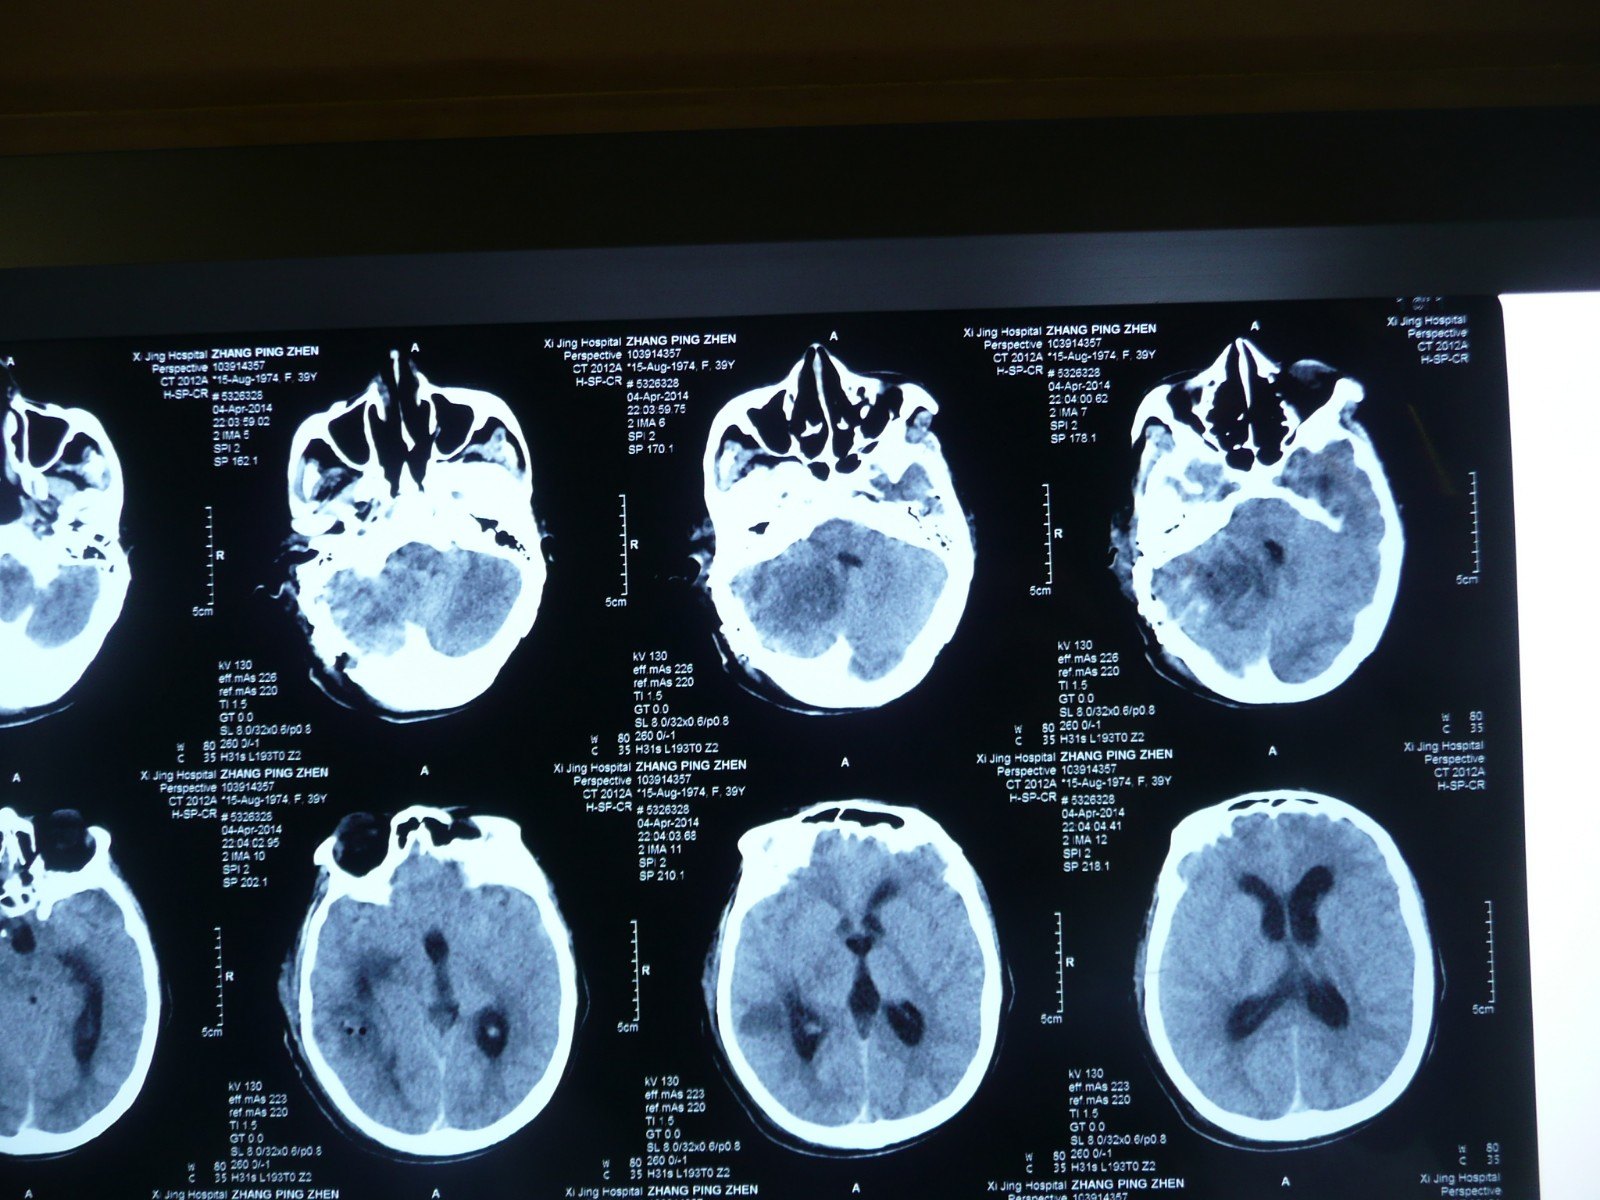

术后即刻ct:小脑幕缘高密度影,考虑造影剂渗出.

左小脑占位,是否有明显尾征,能确定小脑幕脑膜瘤么